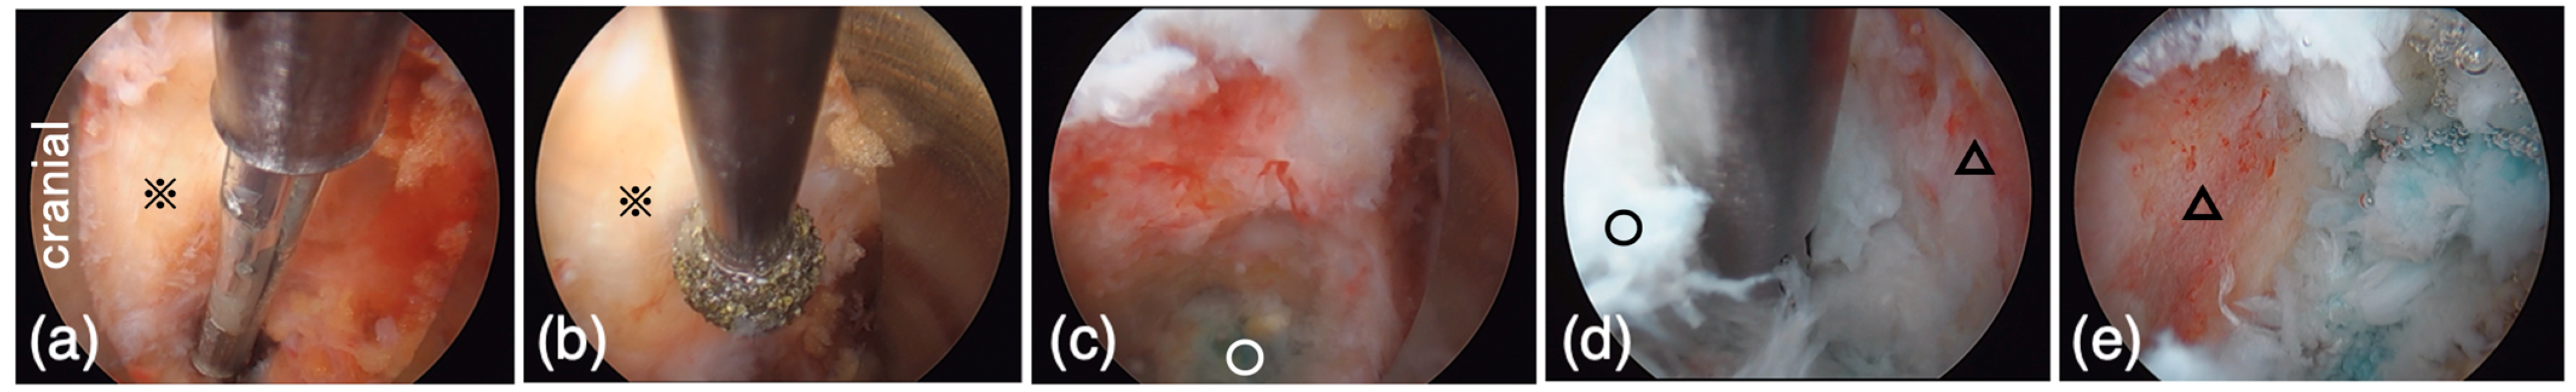

(a) According to the C-arm fluoroscope, PPS entry points (p), posterior-lateral entry for the cage (※), and incision for bone harvesting (△) were marked on the skin. (b) PPS was inserted under fluoroscopic guidance. (c) The caudal set screws were fixed with the cranial side of the rods kept a certain distance from the screw head. (d) The spondylolisthesis of the cranial vertebra was corrected by tightening the set screws.

2.5.3. Reduction of Spondylolisthesis Using PPS

Pedicle screws were inserted percutaneously under fluoroscopic guidance using the Pisces Spinal System® (Japan Medical Dynamic Marketing, Tokyo, Japan) (Figure 3b). The screws’ diameter and length were determined by preoperative CT scan. Rod length was selected, and two rods were inserted bilaterally. The caudal set screws were fixed with the cranial side of the rods kept a certain distance from the screw head (Figure 3c). The spondylolisthesis of the cranial vertebra was then corrected by tightening the set screws (Figure 3d).